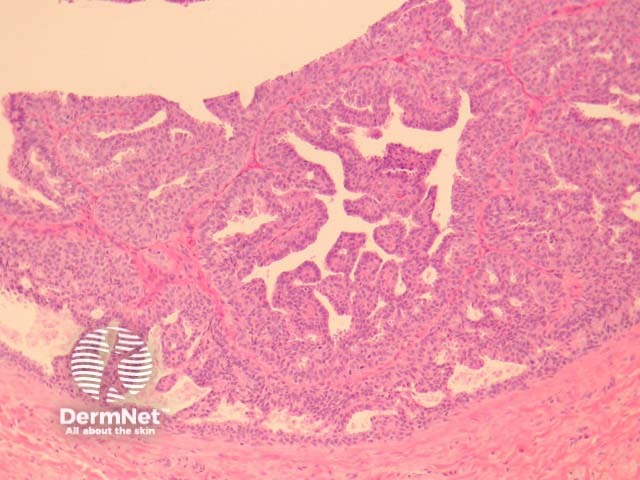

Hidradenoma papilliferum is a well-circumscribed dermal nodule, usually without connection to the overlying epidermis (figure 1). Tubules and broad, elongated fronds form an arborizing pattern and are lined with a double-layered epithelium (figures 2, 3). The inner layer is comprised of cuboidal myoepithelial cells and the outer is tall columnar apocrine cells with a pale eosinophilic cytoplasm, which may demonstrate decapitation secretion. Larger fronds may have a fibrous core. Fibrous tissue surrounding the tumour may be compressed to form a pseudocapsule.

Figure 2

Figure 3